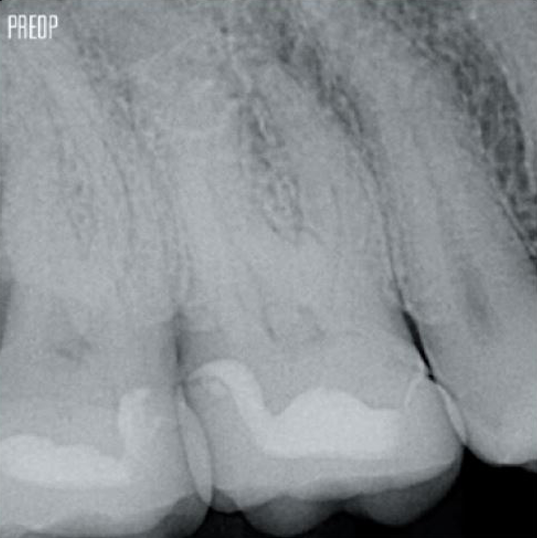

Fotos cortesia do Dr. Ahmed Salman

A retenção da dentina serve como base crítica para uma restauração de qualidade após o tratamento do canal radicular. Quanto mais dentina for preservada durante um tratamento endodôntico, mais opções haverá para realizar uma restauração bem-sucedida e durável.1

O tratamento bem-sucedido do canal radicular começa com o acesso adequado à câmara pulpar. O procedimento ideal fornece acesso aos orifícios do canal radicular com perda mínima de dentina.

Uma cavidade endodôntica conservadora (CEC) é recomendada com o sistema TruNatomy®.